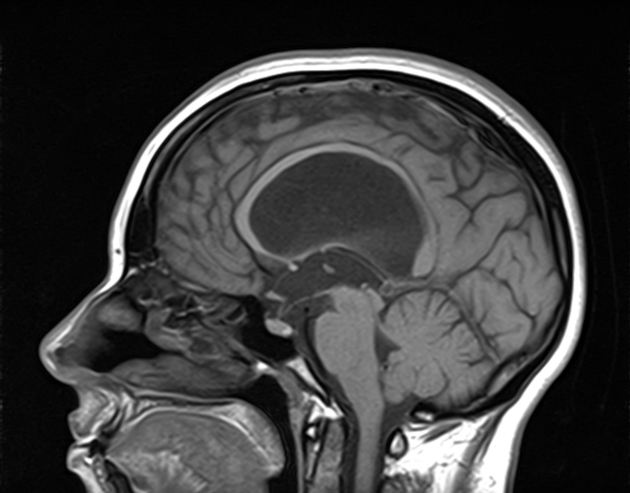

dandy walker malformation

This case illustrates a classic Dandy Walker malformation with associated aqueduct stenosis and obstructive hydrocephalus, a common associated feature

(although not part of the Dandy walker triad: